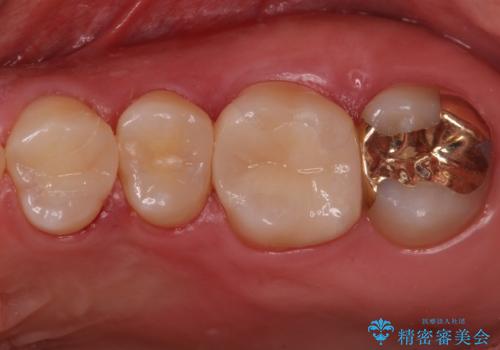

奥歯が欠けた セラミックインレーでの修復後、ナイトガード装着